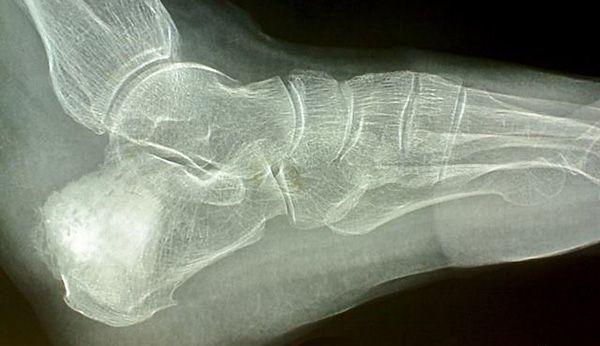

II型毛发-鼻-指(趾)综合征(TRPS II)患者的主要症状是:骨骼与关节发育畸形,面部异样,智力残障,皮肤,牙齿,汗腺和指甲出现异常等,即此染色体异常病症会影响到机体的多个部位,如:毛发,鼻,手指和脚趾等。另外,此病患者还可能有软骨瘤(一种良性肿瘤)的并发症。某位患者身上可能会有几个到上百个不等的软骨瘤。

通常在婴儿期,此类肉瘤即开始生长,延续至幼年早期。当患者步入青少年时期,肉瘤便停止生长。根据软骨肉瘤生长的位置不同,可能会使得患者出现各种不同的症状,诸如:疼痛,关节部位无法移动,血管和脊椎受损等。此病患者的骨密度可能比正常值偏低,无论在胎儿期还是婴幼儿期都比正常人生长发育更为缓慢,因而患者身材往往过于矮小。

TRPS II患者的手指和脚趾的某块或更多的骨骼末端都会呈现病态的锥型状,而且都很脆弱,外形也出现异常。此病的患儿通常关节可运动幅度变大。往往软骨瘤在婴幼儿早期即开始生长,关节僵化,四肢活动能力渐渐弱化。

TRPS II患者通常会出现髋关节发育不良的症状,通常在婴幼儿期即会出现此类症状,成年了之后症状会加重。患者的典型相貌特征是:眉毛浓密,鼻梁过宽,鼻尖圆滑,鼻和上嘴唇的间距过大;上嘴唇偏薄;婴幼儿牙齿的数量出现异常。几乎所有的此病患者头发稀疏。男性患者可能尤其受脱发困扰,许多患者青春期一过后头发便所剩无几。部分此病患儿在短时期内还会出现皮肤松弛的症状,但是一段时间过后,症状会自行消失。此外,TRPS II患者还可能会出现多汗的症状,但大多数患者的智障是属于轻度的。